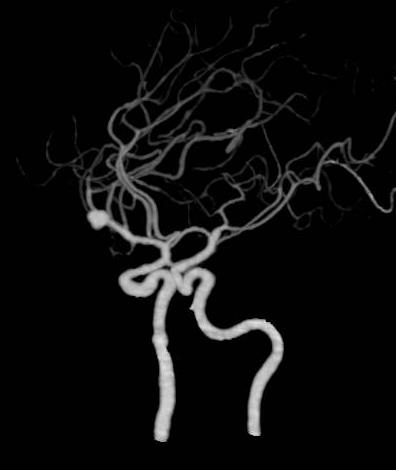

颅脑CTA示左侧大脑中动脉分叉处动脉瘤